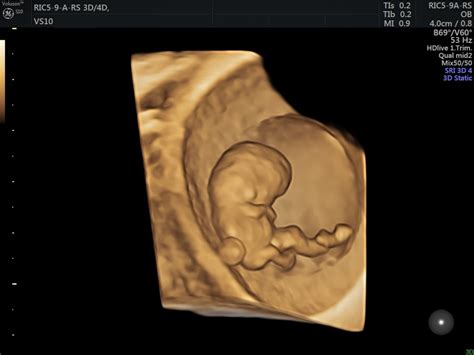

3D ir 4D echoskopija yra inovatyvūs tyrimai, leidžiantys matyti ryškų ir erdvinį vaisiaus vaizdą. 3D ultragarsas pateikia statinį, erdvinį vaizdą, leidžiantį detaliai matyti išorinius vaisiaus bruožus, tokius kaip veidukas, rankytės, kojytės. Tai suteikia tėvams galimybę pirmą kartą „pamatyti“ savo kūdikį dar prieš gimimą, sustiprinant emocinį ryšį.

4D ultragarsas, skirtingai nuo 3D, yra vaizdas realiuoju laiku. Jis leidžia stebėti vaisiaus judesius, mimiką, čiulpimą, žiovulį ar rankyčių judesius. Tai suteikia dar išsamesnį vaizdą apie negimusio vaiko gyvenimą.

Dažniausiai 3D ir 4D ultragarsiniai tyrimai atliekami tarp 24 ir 34 nėštumo savaičių, o apie 27-28 nėštumo savaitę laikoma idealiausiu laiku. Šiuo laikotarpiu kūdikio veido bruožai jau būna susiformavę, jis būna užsiauginęs šiek tiek riebalinio sluoksnio ir dar turi pakankamai vietos judėti, todėl galima gauti aiškius ir detalius vaizdus. Nerekomenduojama tyrimo nukelti į nėštumo pabaigą, nes kūdikis susilenkia ir tuomet tampa sunkiau pamatyti jo veido bruožus.

Nors 3D ir 4D ultragarsas nėra būtini mediciniškai, jie suteikia papildomos informacijos apie vaisiaus išorinius bruožus ir leidžia tėvams geriau susipažinti su savo būsimu vaiku. Šie tyrimai yra visiškai saugūs tiek mamai, tiek vaisiui ir trunka apie 30-45 minutes.